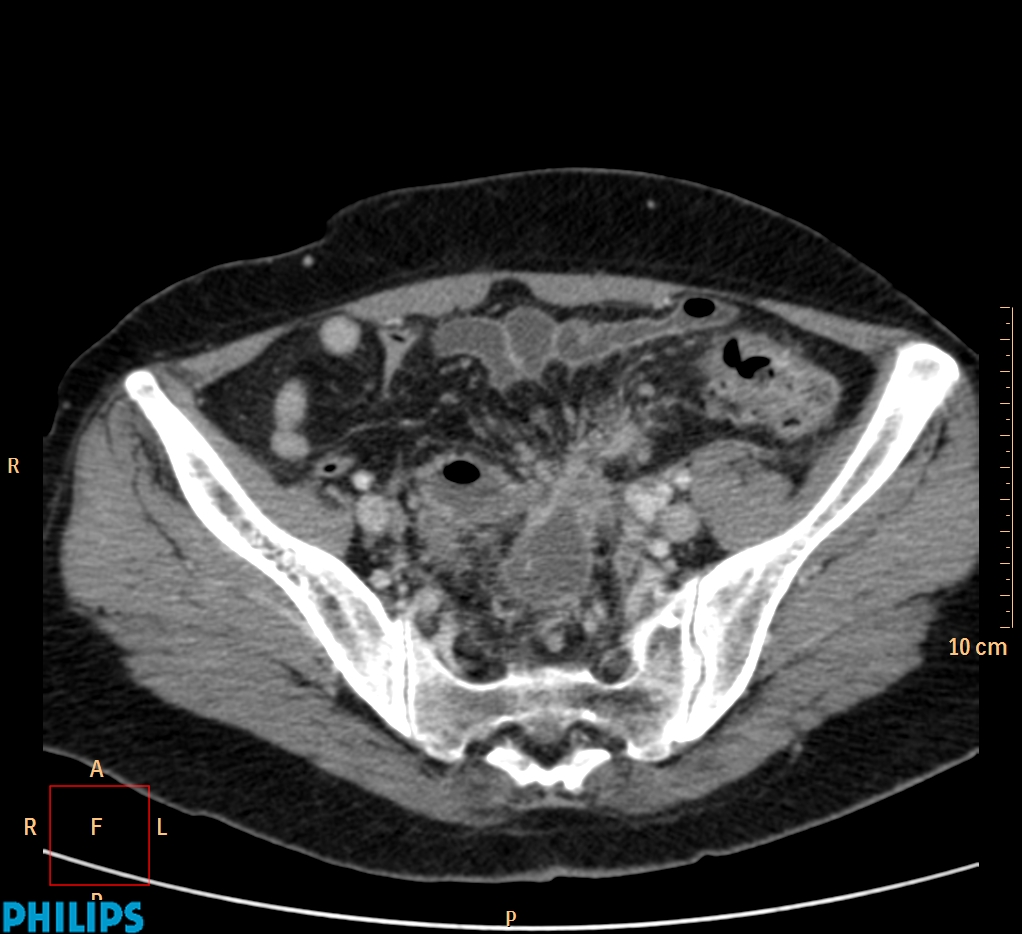

ΕΚΚΟΛΠΩΜΑΤΑ ΠΑΧΕΟΣ ΕΝΤΕΡΟΥ Posted by ΙΠΠΟΚΡΑΤΕΙΟ ΙΩΑΝΝΙΝΩΝ | Dec 16, 2020 | ΠΕΠΤΙΚΟ | 0 ΚΛΙΝΙΚΑ ΣΤΟΙΧΕΙΑ – ΙΣΤΟΡΙΚΟ υποτροπιάζοντες επαναλαμβανόμενοι πυρετοί κυρίως απογευματινές ώρες ΕΡΓΑΣΤΗΡΙΑΚΟΣ ΕΛΕΓΧΟΣ ΑΠΕΙΚΟΝΙΣΤΙΚΟΣ ΕΛΕΓΧΟΣ διακρίνονται τα αποστήματα στην ελάσσονα πύελο, καθώς και εκκολπώματα με εικόνα πάχυνσης του τοιχώματος του σιγμοειδούς ΣΥΖΗΤΗΣΗ